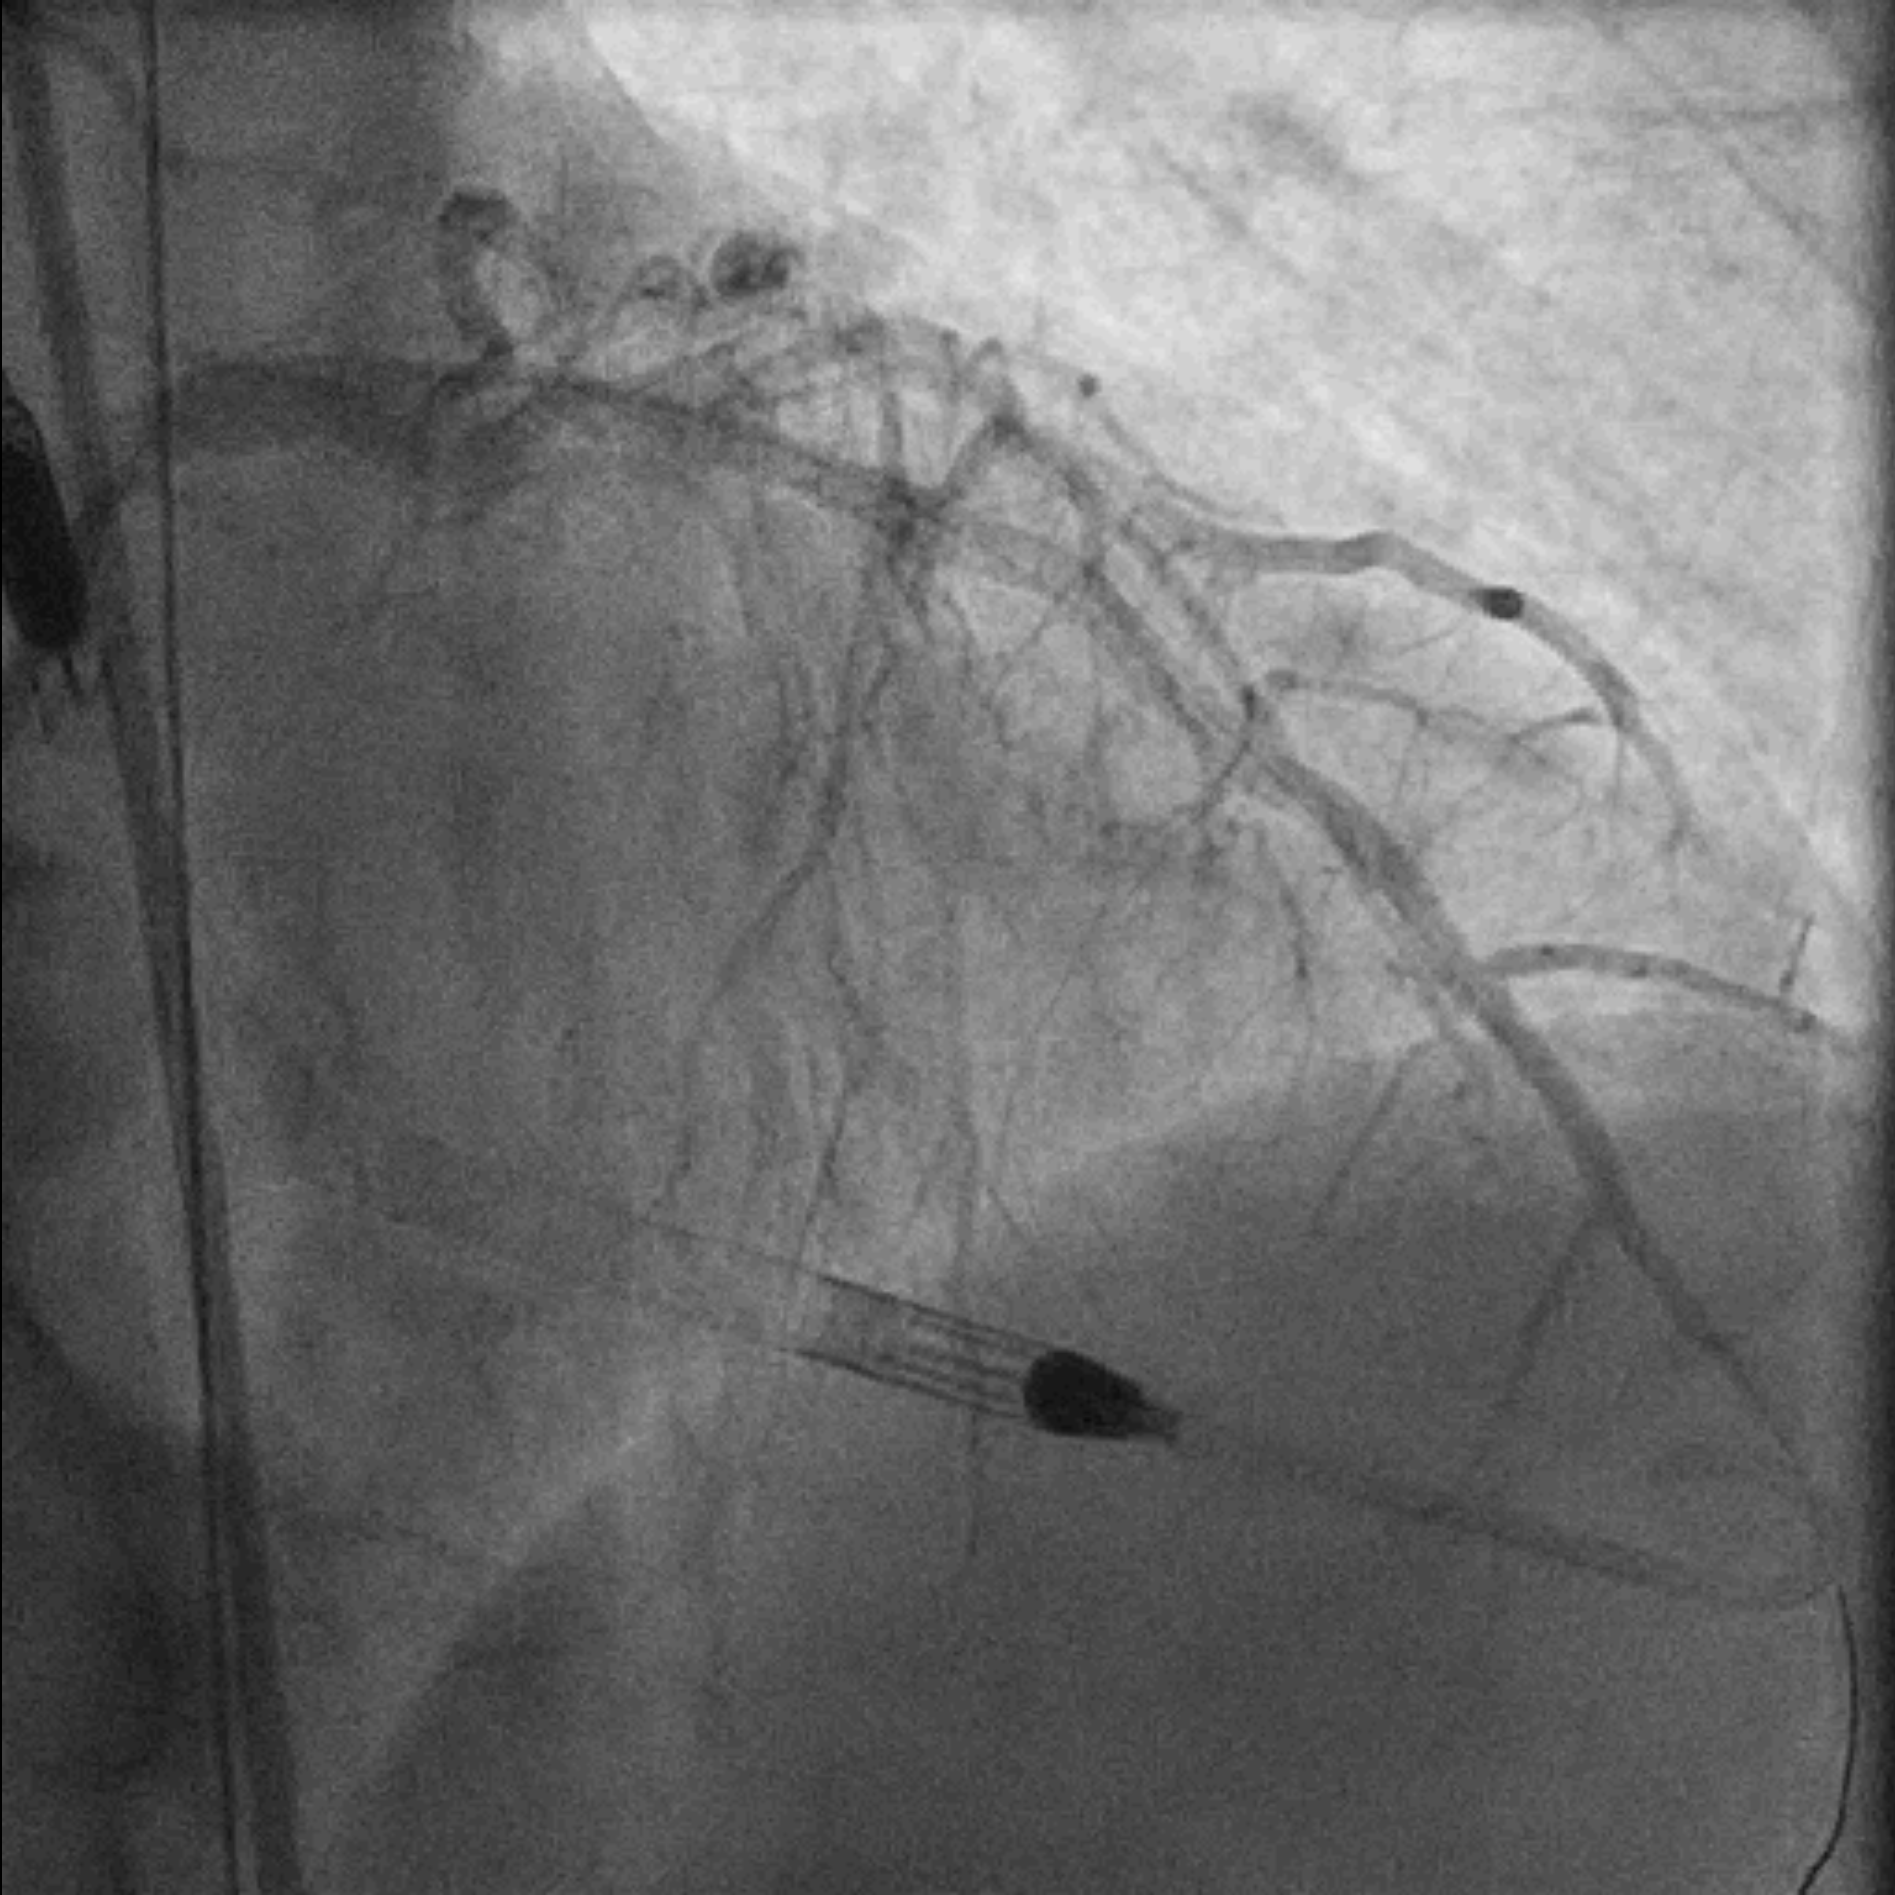

EBU 3.5 7Fr was used to engage left main common artery. Proximal LAD lesion was crossed with a Corsair Pro XS supported Fielder XT-R. Dottering with Sapphire 2.0/15 was unable to achieve flow in LAD. Low pressure inflation of 2.0 mm x 15 mm semi-compliant balloon at ostial to proximal LAD restored TIMI II flow. IVUS demonstrated organised clot in pLAD and plaque extension into LM. A 3.5 mm x 48 mm DES was deployed over mid-LM to mLAD at nominal pressure. The stent was further optimized with 5.0 mm x 6 mm and 4.0 mm x 15 mm non-compliant balloons under IVUS guidance. Intracoronary Adenosine was administered to improve coronary flow. Final angiogram showed TIMI III flow with no immediate complications. Faint retrograde flow to distal RCA was observed. A brief attempt to open RCA was made as the chronicity of the lesion was uncertain. However, Fielder XT-A supported by Corsair Pro XS failed to cross the lesion and the procedure was aborted.